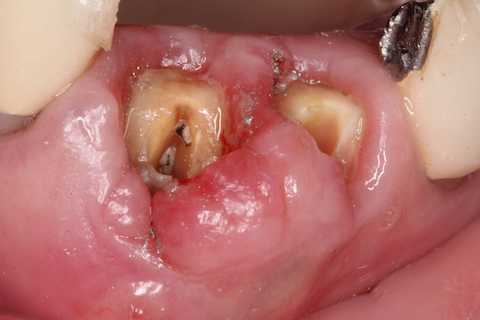

70代女性、右上4、歯根破折前回のつづきこの歯は1年ほど前に前医で治療を受けた時に、割れているので近いうちに抜歯になると言われたそうだ。そこはインプラントをしている歯医者だったので、インプラントは勧められなかったの?とお訊きしたら、そんなことは抜く直前しか言われないそうだw1週間後、とりあえず抜いてみた。かなり歯質は薄くなっていたので、抜くのも難しい。抜歯鉗子で握り潰してしまいそうだ。抜いて見てみると、完全離断ではなかったが、クラックがあるかもしれなかったので、抉り割ってみた。あとは綺麗にして、スクリューポストを入れて再建していくのだが、根尖口とは違うところにリーマーが飛び出して折れていた。また、根管充填材はFeS(硫化鉄)で黒くなっていた。これは硫酸塩還元細菌が生息していたということを意味しており、根管内は細菌で汚染されていたということだ。緊密な根管充填は垂直加圧法以外では見たことがない。所詮、人間のすることなどこの程度だ。これでは遅かれ早かれ歯はだめになってしまう。神経を取るなど最初からしないのが一番良いのだが、なぜしないのだろうか? 歯科医師は歯学部を卒業するまでに完全に洗脳されてしまうようだ。今日は再建から再植まで。根尖はリーマーが突き抜けて折れていた部分と、本物の根尖口らしいところを開拡して充填した。では時系列でどうぞ

70代女性、右上4、歯根破折前回のつづきこの歯は1年ほど前に前医で治療を受けた時に、割れているので近いうちに抜歯になると言われたそうだ。そこはインプラントをしている歯医者だったので、インプラントは勧められなかったの?とお訊きしたら、そんなことは抜く直前しか言われないそうだw1週間後、とりあえず抜いてみた。かなり歯質は薄くなっていたので、抜くのも難しい。抜歯鉗子で握り潰してしまいそうだ。抜いて見てみると、完全離断ではなかったが、クラックがあるかもしれなかったので、抉り割ってみた。あとは綺麗にして、スクリューポストを入れて再建していくのだが、根尖口とは違うところにリーマーが飛び出して折れていた。また、根管充填材はFeS(硫化鉄)で黒くなっていた。これは硫酸塩還元細菌が生息していたということを意味しており、根管内は細菌で汚染されていたということだ。緊密な根管充填は垂直加圧法以外では見たことがない。所詮、人間のすることなどこの程度だ。これでは遅かれ早かれ歯はだめになってしまう。神経を取るなど最初からしないのが一番良いのだが、抗生剤も普及しているにもかかわらず。なぜこんなことを100年以上もし続けるのだろうか? 歯科医師は歯学部を卒業するまでに完全に洗脳されてしまうようだ。今日は抜歯するまで、まずはレントゲン写真でのbefore/afterだ。beforeリーマーが折れこんでいるのが見えると思う。after抜歯はかなり手こずった。壊しそう。。抜歯窩は膿瘍を丁寧に搔爬し、洗浄しておくつづく